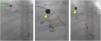

A dedicated CT scan of the liver showed new haematomas forming around the liver, and a 1.5cm pseudoaneurysm at the subdiaphragmatic surface of segment VII of the liver (Fig. 1).

A subsequent angiogram done via a right femoral approach confirmed the presence of this pseudoaneurysm which was being supplied by the superior branch of the right phrenic artery. Embolisation coils were placed in the pseudoaneurysm sac and in its feeding artery (Fig. 2).